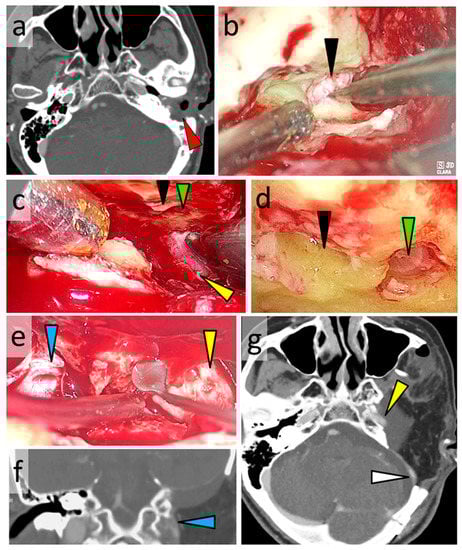

3.6.2. Case 2